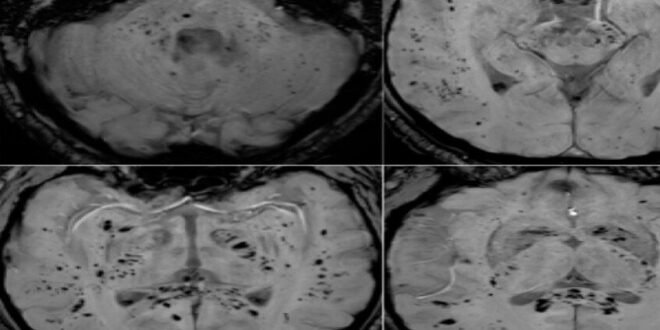

أظهر تحليل صور بالرنين المغناطيسي أن فيروس كوفيد-19 يترك أثرا لا يُمحى في الدماغ، ويستمر تأثيره حتى بعد التعافي التام.

وأوضح الباحث الرئيسي الدكتور كيران تاباليا أن الفريق استخدم طرق التصوير بالرنين المغناطيسي متعددة الوسائط لدراسة المادة الرمادية والبيضاء في الدماغ، وهي مهمة للذاكرة والوظائف الإدراكية والصحة العامة للدماغ. ووجد الباحثون اختلافات ملحوظة في أنسجة الدماغ وموادها الكيميائية العصبية وشدة الإشارة وبنية الأنسجة لدى المتعافين من كوفيد-19، حتى في حالات الإصابة التي اعتبرت بسيطة.

وأضاف تاباليا: “تبين أن التغيرات في أنسجة الدماغ مرتبطة بشدة الأعراض”، ما قد يفسر مشكلات إدراكية طويلة الأمد مثل تدهور الذاكرة والتركيز، والتي قد تستمر لشهور أو حتى سنوات بعد الإصابة.